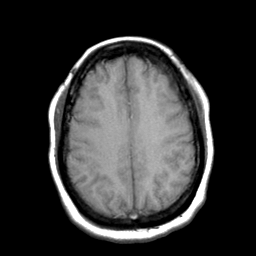

Cerebral hemorrhage, MR Study mr-t1 -- Slice #17

[Home][Help][Clinical] Slice 17